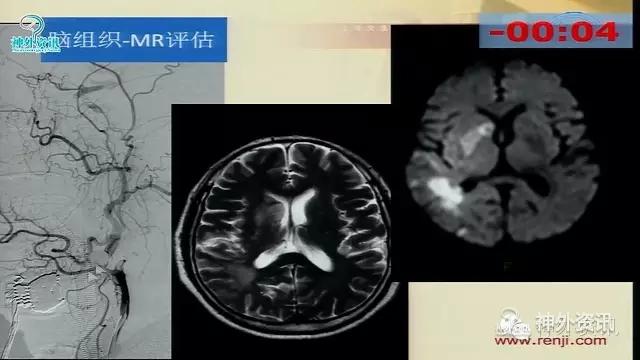

万杰清教授:慢性颈动脉闭塞再通技术及临床效果

擅长脑血管病的治疗研究工作,对动脉瘤性蛛网膜下腔出血的规范化、个体化治疗有独到之处,已成功治愈各种复杂性脑血管3000余例;擅长脑血管病的微创血管内介入和显微外科治疗,包括急性破裂出血的脑动脉瘤、脑血管畸形和硬脑膜动静脉瘘的栓塞治疗,以及颈动脉内膜切除和血管内支架治疗颈动脉狭窄预防脑梗死等。.曾获得仁济医院首届十佳青年,第二医科大学新长征突击手和优秀仁济人—白求恩式的好医生称号,2010仁济医院首届优秀青年临床骨干。分获上海市科技进步二等奖和三等奖。已发表论文30余篇,SCI收录7篇。